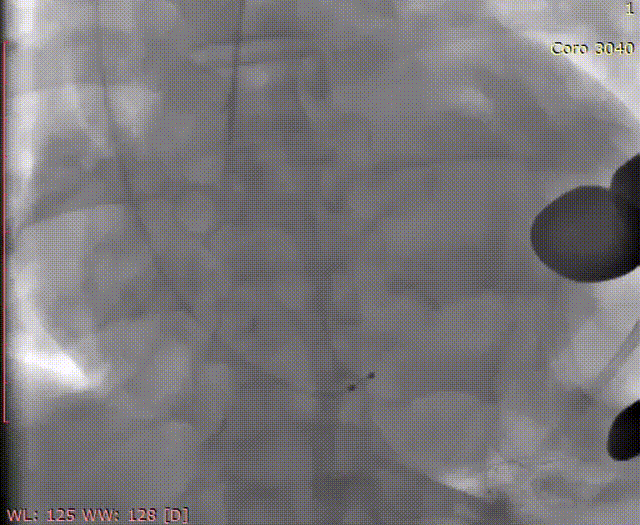

猪尾在窦上造影